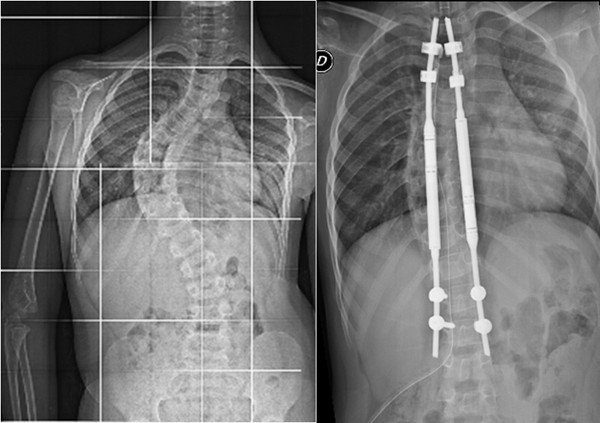

Le tradizionali 10-15 operazioni necessarie sin dai primi anni di vita per correggere la curva della colonna vertebrale (in alcuni casi anche di 50° con prospettive di peggioramento pari a 10/15° l’anno) vengono infatti sostituite da un unico intervento che si esegue intorno ai 2 anni e mezzo d’età del piccolo. Consiste nell’impianto di alcune barre di titanio lungo la colonna vertebrale che, a differenza della tecnica consueta, si allungano magneticamente con un meccanismo telecomandato dall’esterno, in modo indolore, senza ricovero né operazione e seguendo naturalmente l’iter di crescita del bambino.

Nelle foto si vede una scoliosi infantile prima del trattamento e dopo con le barre in titanio telecomandate. La scoliosi è scesa da 80° a 16°.